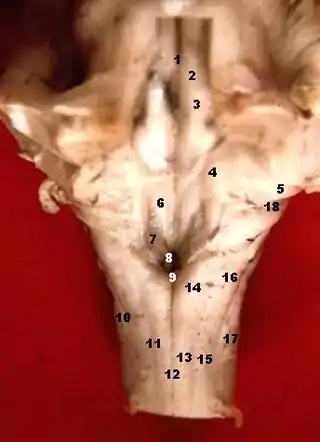

Figura que muestra el modo de inervación de los músculos Recti medialis y lateralis del ojo. Tallo cerebral humano, vista posterior.

Tallo cerebral humano, vista posterior.